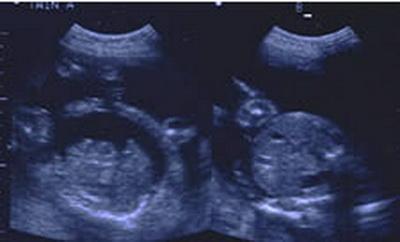

Когда паре Шэннон и Майк Гимбел (Shannon, Mike Gimbel) сообщили, что им придется умертвить одного из близнецов, чтобы другой смог выжить, это стало настоящим кошмаром для родителей.

У близнецов было редкое расстройство, называемое синдром фето-фетальной трансфузии, при котором дети соединены кровеносными сосудами и один близнец буквально забирает жизнь у другого. Если оставить двоих близнецов, то у обоих риск смерти составляет 90 процентов.

Сначала Гимбелы решили расстаться со слабым близнецом, но появилась альтернатива. С помощью лазеров врачи пережгли кровеносные сосуды, соединяющие близнецов, разделив их. Обе девочки-близнеца выжили и благополучно появились на свет.